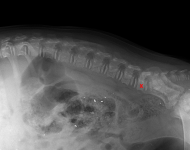

(1) 7 týdnů VD

(1) 7 týdnů VD

(1) typ 3

(1) typ 3